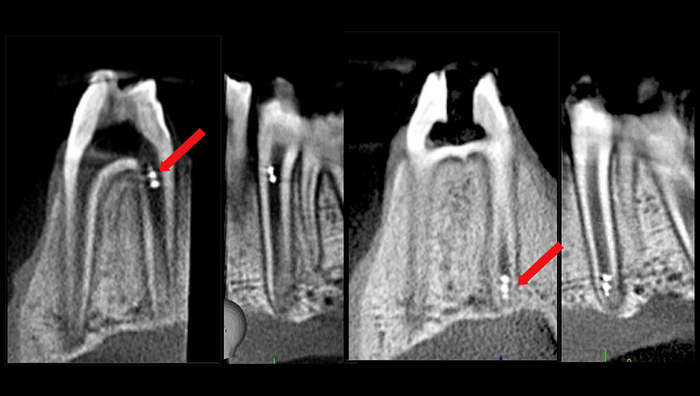

IMAGE: MAGNETICALLY ACTUATED 3D MOLDED ROBOTS ARE CONTROLLED PRECISELY TO TARGET THE APICAL REGION OF THE ROOT CANAL UNINTERRUPTED BY THE SURROUNDING PERIODONTIUM AS VISUALIZED AND TRACKED BY CBCT. view more

In addition, the research team showed the unique ability of track the microrobots in real-time using existing imaging technologies such as intraoral scanner, dental x-ray, and cone-beam computed tomography that were capable of locating the helicoids in the intact tooth canal.

“Importantly, we demonstrated in an ex vivo model that the robots could be controlled by the magnetic field without interruption by the soft and hard tissue surrounding the teeth. In addition, they showed tremendous maneuverability from the top to bottom of the canal,” notes Dr. Karabucak, who explains the magnetic field for both of the endodontic systems tested would be generated by a small device in the oral cavity.